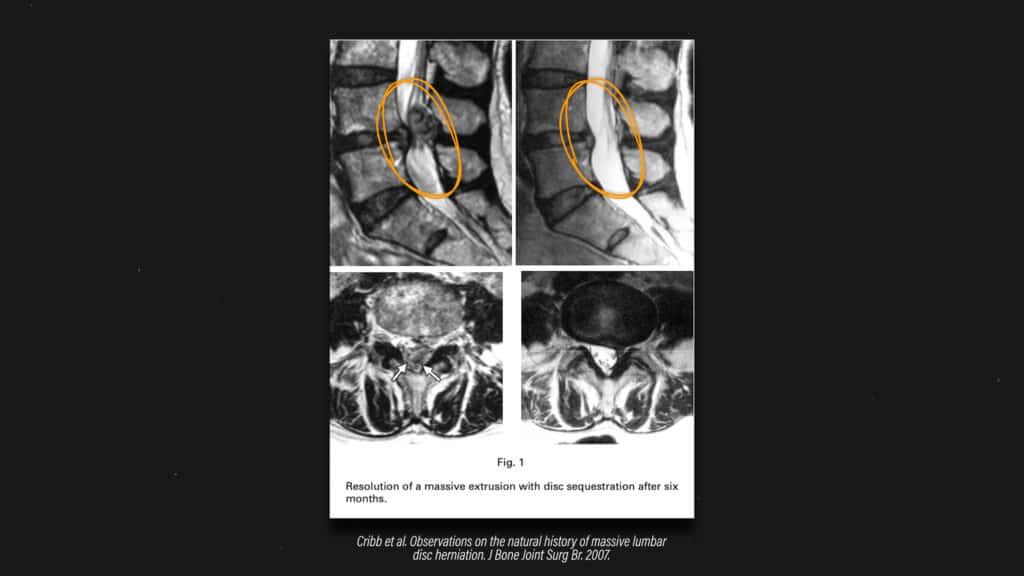

Na sreću, diskus hernije mogu da zarastu. Evo slike primera pacijenta kod kojeg je došlo do značajne regresije diskus hernije tokom vremena.

diskus hernija lečenje